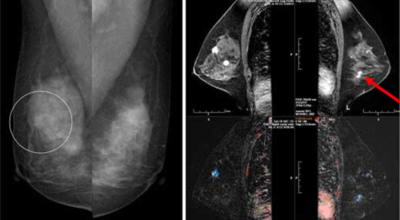

2. 유방암 초기증상 - 유방의 혹

보통 응어리가 잡히는 분들의 40%는 물혹으로 가벼운 질병으로 바로 치유가 되는 경우가 많은데요 20~30%의 확률로 유방암 초기증상일 가능성이 있다고 하죠. 따라서 매일같이 자신의 가슴을 마사지 해주시다 어느 날 응어리가 잡히게 된다면 유방암 검사 초기에 받아 보시기를 권해 드립니다.